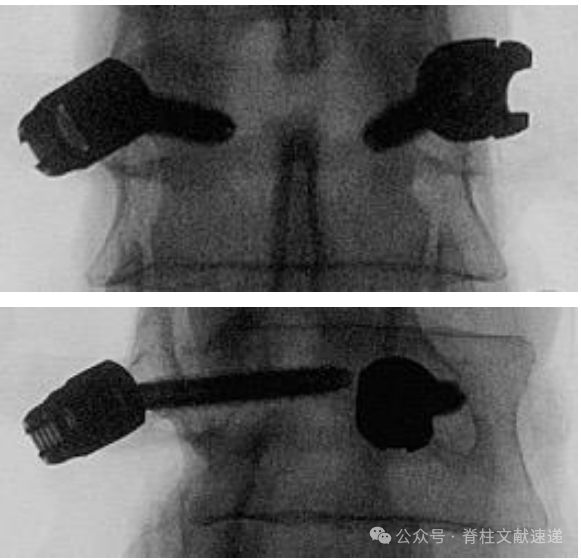

正位、侧位透视大家很熟悉,斜位透视做一介绍。斜位透视法也叫椎弓根轴位透视法或“猫头鹰眼”透视法,透视管球在矢状位和轴位均平行于目标椎弓根,这时椎弓根就像猫头鹰的眼睛,一个“睁圆”(目标椎弓根),一个“闭着”(对侧椎弓根显示较窄)。透视时,将C臂从标准正位进行旋转即可实现,图中的a角约20-30度。

第一次,医生找出了68%的2mm偏差的螺钉。第二次,医生找出了67%的2mm偏差的螺钉。C臂透视筛查椎弓根螺钉错位的敏感性不高。 添加倾斜视图可以提高检测螺钉错位的特异性,但不未提高灵敏度和准确性(有别的文献认为提高了灵敏度和准确性,莫衷一是)。

在术中透视时,获得标准正位、标准侧位会提高评估的准确性。而实际情况经常是不标准的透视影像。终板不平行、棘突不居中、椎体后缘双影、目标椎体不在视野中间等会影响判断。标准正位是最重要的评估影像。在可疑、拿不准的时候,补充斜位透视是有帮助的,不妨一试。